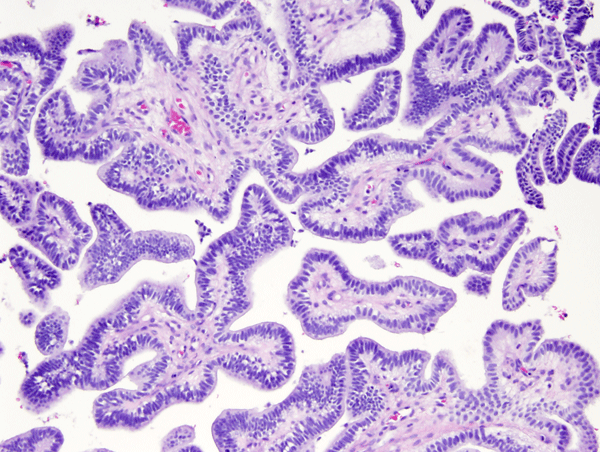

Choroid plexus tumors affect mostly children and young adults. They are a continuum which includes choroid plexus papilloma-CPP (WHO grade I), atypical CPP (WHO grade II) and choroid plexus carcinoma-CPC (WHO grade III). CPC is most common in very young children and is seen in older patients. In children, CPP and CPC arise in both, lateral and fourth ventricles. In adults, CPP is more frequent in the fourth ventricle and sometimes arises in the cerebellopontine angle. CPP is seen in the Aicardi syndrome, an X-linked syndrome in females, characterized by agenesis of the corpus callosum, chorioretinal lacunae, and infantile spasms. CPC occurs in the rhabdoid tumor predisposition syndrome, caused by germline mutations of the INI1 gene. Choroid plexus tumors cause hydrocephalus and increased intracranial pressure by blocking CSF pathways and by oversecreting CSF. CPC can also seed the subarachnoid space. Both, CPP and CPC have a papillary basic structure. In CPP the papillae are covered by a single layer of benign epithelial cells, similar to normal choroid plexus. In CPC the tumor cells are multilayered, atypical, and mitotic, and the papillary structure may be effaced such that the tumor appears solid.